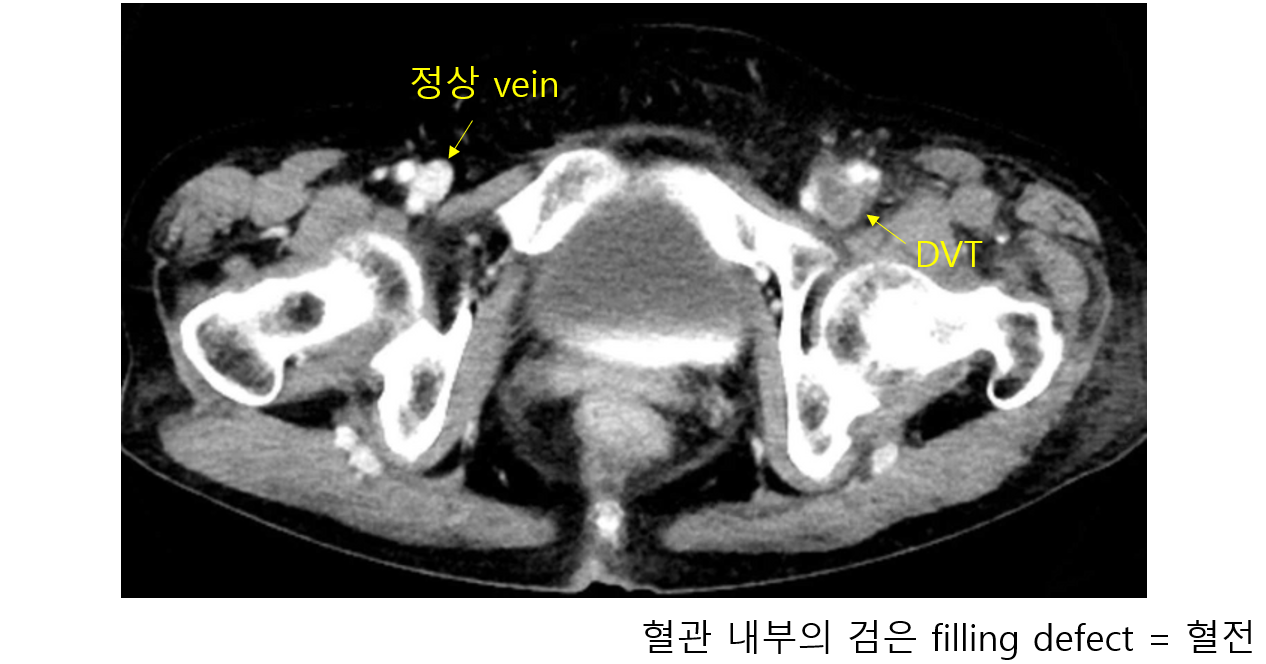

2) 영상검사

(2) 정맥조영술(venography): US로 확인하기 어려운 iliac vein 검사에 유용 (CT, MR, invasive 모두 가능)